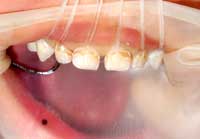

右の2枚の写真は同じお子さんのものです。

両脇の歯が2本とも萌えきると中央の歯は並んでくれるんです。

ですから お母様方には、「両脇の歯が生えてきて押されることで中央の隙間はなくなり、前からは唇の力で、後ろからは舌の力で押されるのでねじれは治ってきます。今の時点で心配する必要はありません。」と説明します。

6才・みにくいアヒルの子の時期

4年後にはこんな歯並びに